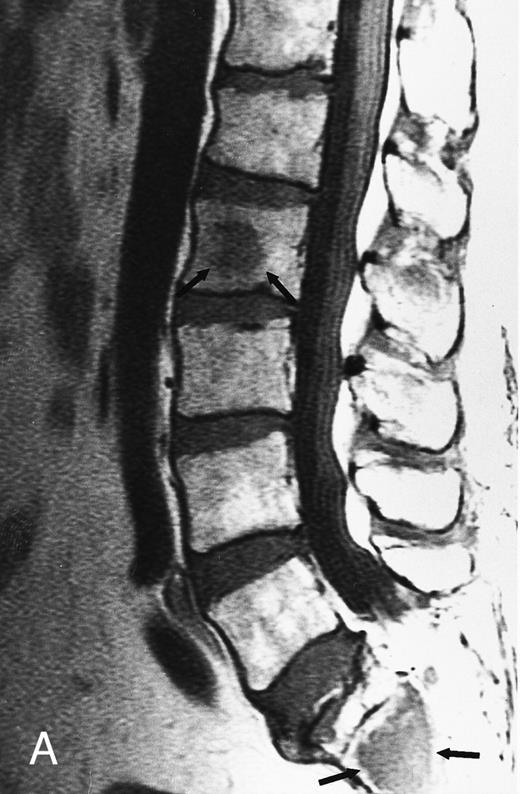

T1-weighted (500/11, TR/TE) sagittal MR images of the lumbosacral spine in a 45-year-old woman before (A) and 40 days after (B) bone marrow transplantation for multiple myeloma. There is a diffuse MR pattern of marrow involvement in (A) (bone marrow plasma cells, 50%; monoclonal protein, 6.0 g/dL). On the posttreatment image, there is definite reinstitution of fatty marrow in the spine and, in particular, around the basivertebral veins, in keeping with partial response to treatment (bone marrow plasma cells, 0.5%; monoclonal protein, 1.6 g/dL).

During the first posttransplantation days, marrow necrosis is seen as a decrease in the signal intensity of the marrow on T1-weighted images and as increased brightness on T2-weighted images. Within 3 months from bone marrow transplantation, a characteristic band pattern appears on T1-weighted MR images of the spine.90 This band pattern consists of a peripheral zone of dark signal and a central zone of bright signal. At histologic examination, the peripheral zone corresponded to repopulating hematopoietic marrow and the central zone to marrow fat.90 Stevens et al90 observed the band pattern in all but 1 of 15 patients within 90 days after bone marrow transplantation and up to a follow-up of 14 months. In 1 patient with relapse of disease, the band pattern evolved to a more homogeneous appearance of the marrow. In our experience, the band pattern gradually evolves into a homogeneous appearance of the marrow after successful bone marrow transplantation.